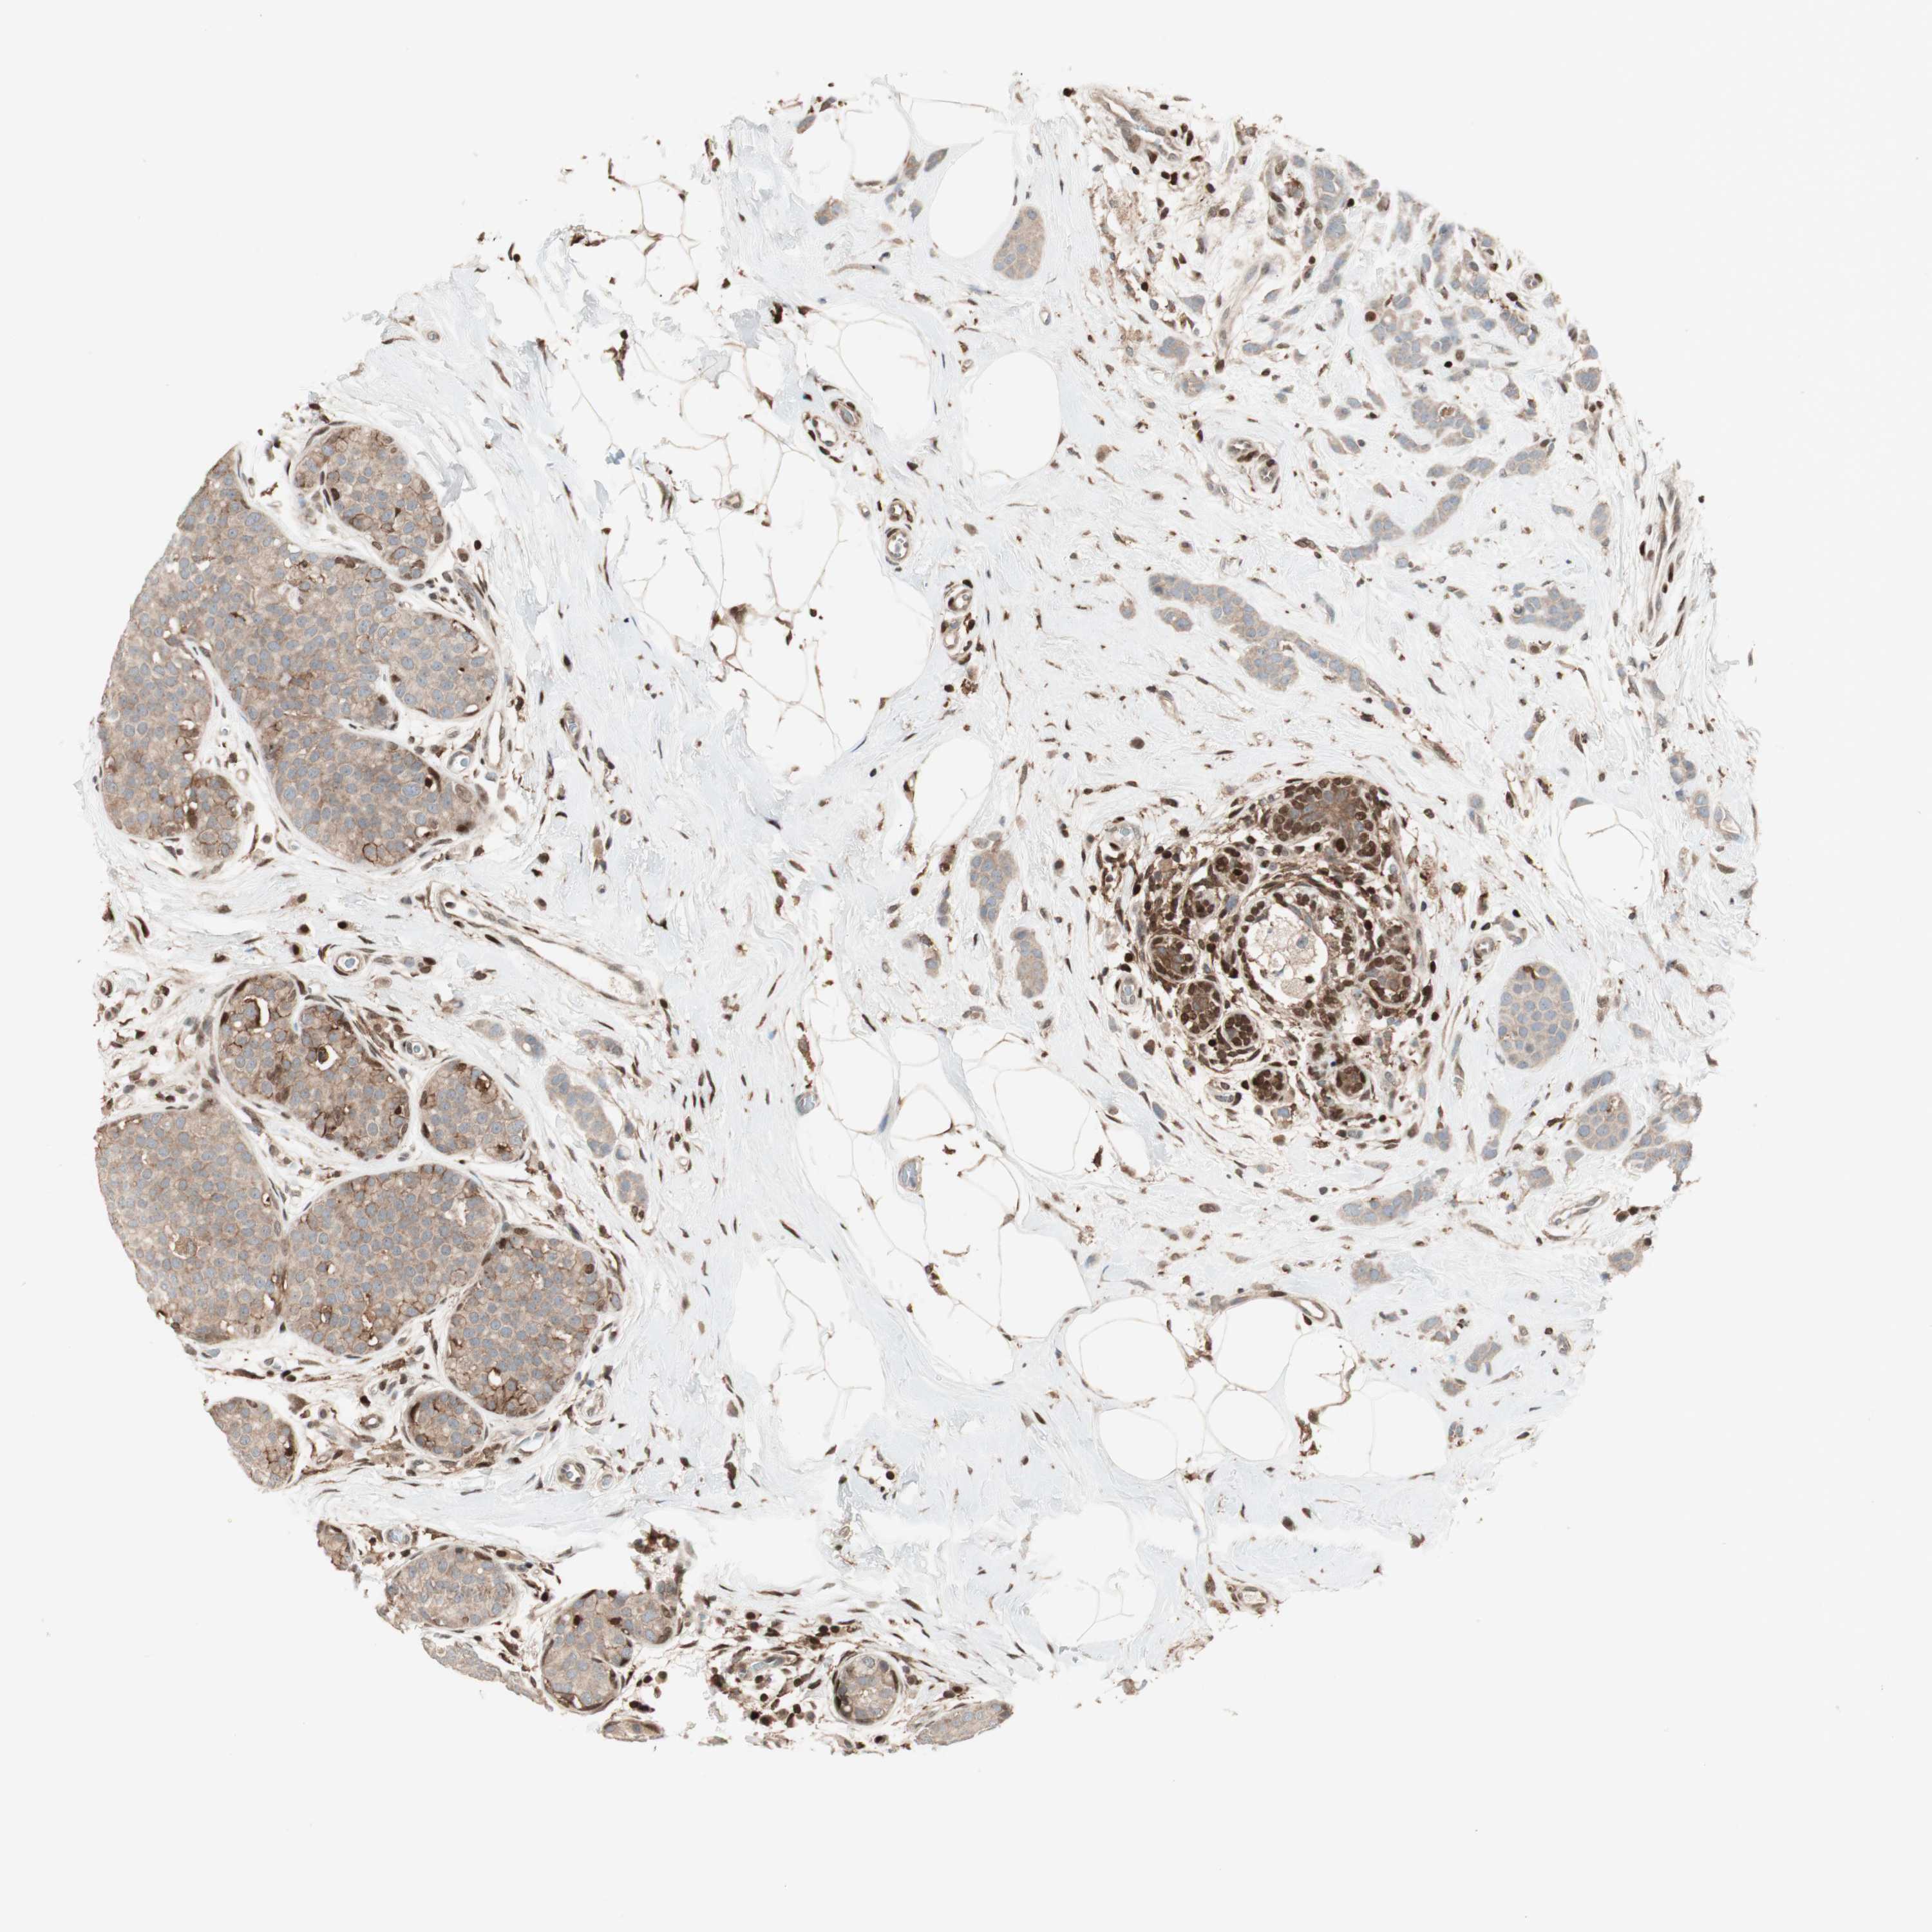

CANCER BREAST CANCER Show tissue menu

BRCA TCGA BRCA VALIDATION PROTEIN EXPRESSION